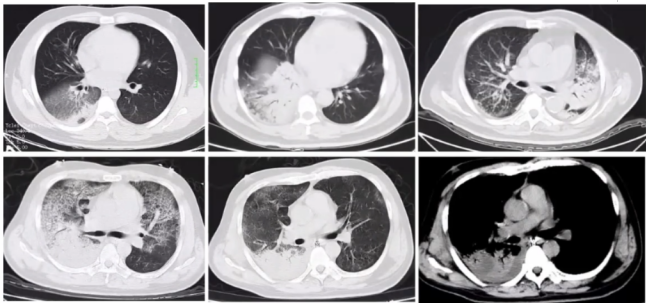

2018年1月至2020年12月我科数据显示,重症腺病毒肺炎好发于中青年男性(图2),不同病毒型的临床表现类似。图2 我科2018年1月至2020年12月重症腺病毒肺炎性别和年龄构成图重症腺病毒肺炎除了呼吸系统表现外,还会出现神经系统、循环系统、消化系统、泌尿系统、网状内皮系统及其他临床表现。呼吸系统主要表现为咳嗽、气促,发热,肺部体征出现晚,以及胸腔积液;神经系统主要表现为精神萎靡、烦躁与嗜睡交替,同时可以出现抽搐、昏迷、中毒性脑病、脑膜炎、脑水肿以及脑疝等;循环系统主要表现为心肌炎、心力衰竭、窦速,心电图T波或ST段改变;消化系统主要表现为呕吐、腹泻、中毒性肠麻痹、消化道出血;泌尿系统主要表现为蛋白尿、出血性膀胱炎;网状内皮系统可出现肝脾大、淋巴结增大表现;其他还有红色丘疹、斑丘疹、扁桃体石灰样小白点等表现。我科对重症腺病毒肺炎患者的统计分析发现,最常见的临床表现是发热、咳嗽、气促、咳痰(图3)。图3 我科2018年1月至2020年12月重症腺病毒肺炎患者症状分布直方图我科2018年1月至2020年12月重症腺病毒肺炎患者统计发现:①白细胞计数可正常,可升高(13%),也可降低(25%),淋巴细胞降低较常见(75%),血小板减少(25%);②心肌酶升高(100%):CK、CK-MB、LDH及MYO升高;③肝功能损害(56%):AST及ALT升高;④肾功能损害(25%):Cr和/或BUN升高;⑤同时存在肝肾功能损害(25%)。重症腺病毒肺炎患者胸部CT可见两下肺为主单发或多发叶段性实变伴或不伴磨玻璃影(GGO)(图4)[2]。国内文献报道了典型重症腺病毒肺炎的影像学,主要表现为实变、GGO、间质病变、胸腔积液(图5)[3]。我科统计重症腺病毒肺炎患者的影像学情况(图6):①双肺实变12例(80%),实变累及5个肺叶1例、累及4个肺叶5例、累及3个肺叶5例。②双肺实变伴GGO 5例(30%);③单肺实变3例(20%),均累及2个肺叶;④单肺实变伴GGO 3例(20%);⑤伴胸腔积液4例(25%),伴气胸1例(6%)。(1)症状:好发于中青年男性,有发热、咳嗽、呼吸困难、肌痛等表现。(2)影像学:实变伴或不伴GGO,伴胸腔积液;动态变化反映病情。